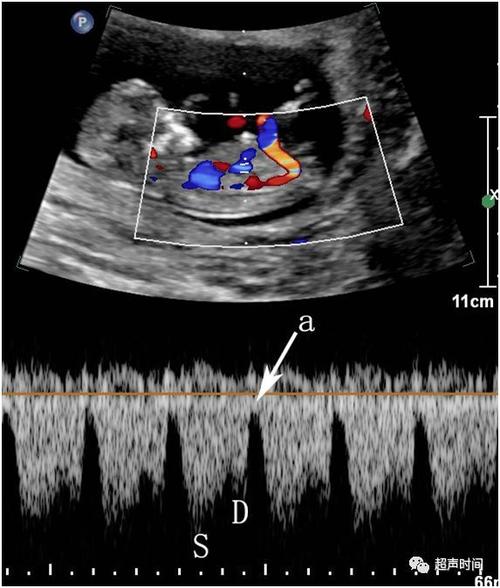

静脉导管血流频谱

胎儿静脉导管血流频谱

胎儿静脉导管频谱

胎儿静脉导管a波反向

静脉导管a波

正常静脉导管频谱图